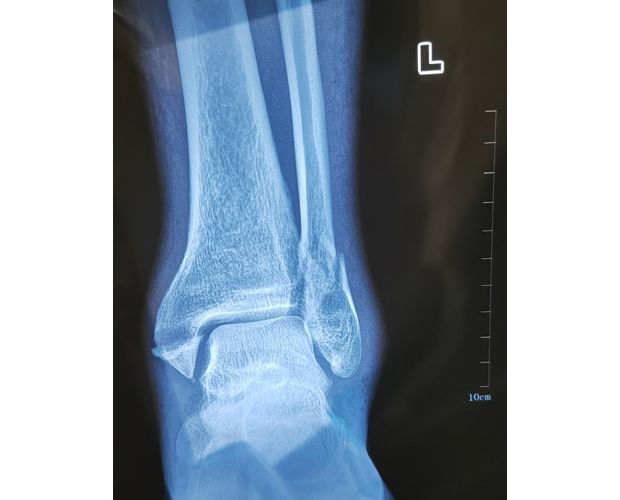

2月4日,何店鎮(zhèn)中心衛(wèi)生院接診一名左踝關(guān)節(jié)外傷患者,經(jīng)影像檢查,確診為左脛、腓骨下段骨折。外科醫(yī)生姜穩(wěn)迅速完成術(shù)前檢查及病情評(píng)估,并與患者及家屬深入溝通治療方案。在患者強(qiáng)烈要求于本院進(jìn)行手術(shù)的情況下,為最大限度保障手術(shù)質(zhì)量與安全,該院特邀請醫(yī)共體牽頭單位——曾都區(qū)人民醫(yī)院脊柱創(chuàng)傷外科專家團(tuán)隊(duì)前來指導(dǎo)。